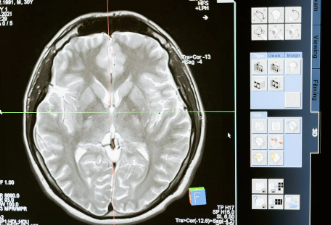

뇌졸증 증상, 예방 및 치료 방법에 대한 이해

뇌졸중은 심각한 건강 문제로, 많은 사람들의 삶을 변화시키는 질병입니다. 뇌졸중은 뇌 혈액 공급이 갑작스럽게 차단되거나 출혈로 인해 뇌 조직에 손상이 생기는 상태를 의미합니다. 이번 글에서는 뇌졸중의 종류와, 주요 증상 그리고 예방방법과 치료 방법에 대해서 같이 알아보겠습니다.